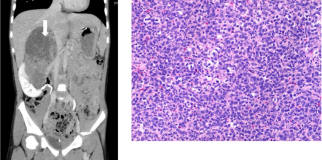

4. Medical Imaging

Medical imaging leverages computer vision to assist in diagnosing and treating diseases. It involves analysing medical images to identify patterns and anomalies.

• Radiology:

Computer vision algorithms help radiologists detect tumors, fractures, and other conditions in X-rays, MRIs, and CT scans. This improves diagnostic accuracy and speeds up the review process.

blog image

• Pathology:

Automated systems analyse tissue samples to identify cancerous cells. This assists pathologists in diagnosing diseases and planning treatments.